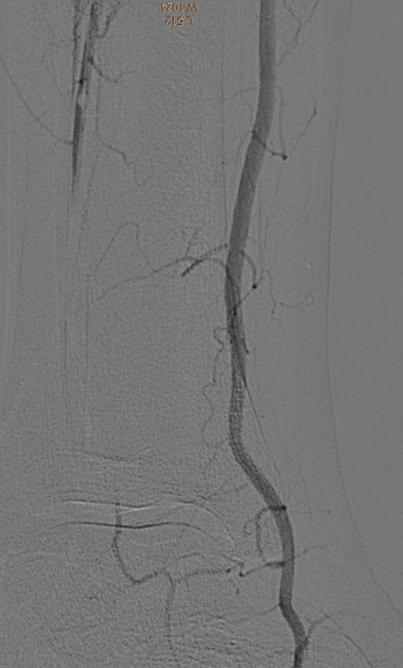

60 КЪСНА РЕВАСКУЛАРИЗАЦИЯ СЛЕД ОСТРА ТРОМБОЗА НА А. СУБКЛАВИА СИНИСТРА –КЛИНИЧЕН СЛУЧАЙ Р. Рунков

62 РЕТРОГРАДНА ПЕРКУТАННА